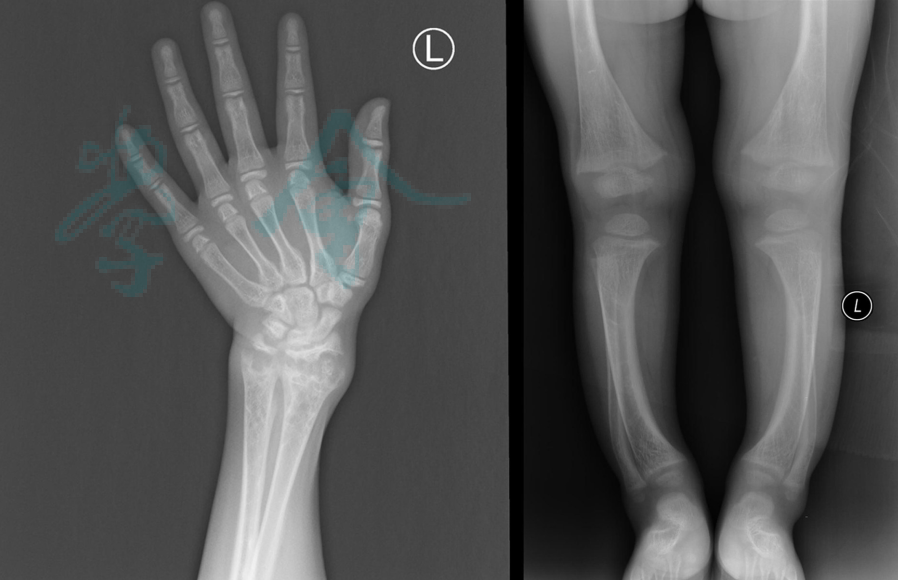

佝偻病因影像学习

6岁双胞胎家族遗传低磷佝偻病,如何治疗?